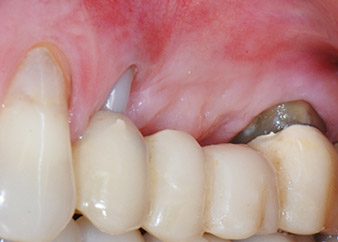

Resultado provisional a los 2 meses

Las figuras 17 y 18 muestran el resultado clínico 2 meses después de la intervención quirúrgica. La pieza 24 tenía una movilidad reducida clase I de Miller y los tejidos blandos no presentaban inflamación. Se evitó el uso de una sonda en este momento para evitar una nueva infección y para no romper la fijación epitelial. El siguiente control se planificó para el momento en el que se reanudara el tratamiento y se colocaran los pilares de cicatrización, 6 meses después de la inserción de los implantes.

Ya en la visita de los dos meses, la movilidad del “elemento dental” residual 24 se había reducido de clase II a clase I de Miller. La fijación del tejido blando se encontraba en el nivel de la pieza dental adyacente 23. Además, no se desarrollaron síntomas endodónticos ni periodontales, por lo que es posible que sea preciso reajustar el pronóstico. Sin embargo, como falta la mayor parte del hueso bucal y proximal y la acumulación de composite se extiende hasta la sección apical de la raíz, por razones biológicas, no cabe esperar un nivel de refijación más alto (Sculean et al., 2008).